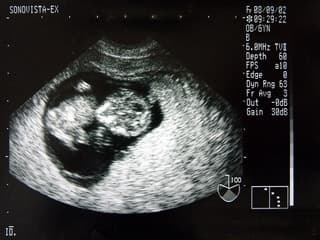

vignette|240px|droite|Échographie d'un fœtus de neuf semaines. L'échographie est une technique d' employant des ultrasons. Elle est utilisée de manière courante en médecine humaine et vétérinaire, mais peut aussi être employée en recherche et dans l'industrie. Le mot « échographie » provient de la nymphe Écho dans la mythologie grecque qui personnifiait ce phénomène et d'une racine grecque Graphô (écrire). Il se définit donc comme étant « un écrit par l'écho ». Le terme « échographie » désigne aussi bien l'acte médical que l'image qui en découle, abrégé au féminin en « une écho ». L'appareil permettant l'échographie est un « échographe ». Les appareils modernes comportent tous une fonction Doppler. C'est pourquoi on parle d'« échographie Doppler » (abrégée en « écho-doppler »). Le médecin, le manipulateur en électroradiologie médicale, ou la sage femme qui pratique une échographie est un « échographiste ». L'échographie moderne est le fruit de plus de de recherche scientifique multidisciplinaire, associant physiciens, mathématiciens, biologistes, médecins, électroniciens et informaticiens. En effet, en 1828, Jean-Daniel Colladon, un physicien suisse, parvient à déterminer la vitesse de propagation du son dans l’eau. Cette découverte est essentielle dans le développement de plusieurs outils reposant sur l’émission et la réception d’ondes sonores. En 1838, un chercheur de l’université de Virginie aux États-Unis, tente de cartographier les fonds marins grâce à un outil basé sur cette méthode. Sa tentative est un échec, mais son idée inspire les inventeurs du sonar pendant l’entre-deux-guerres, qui disposent alors de moyens technologiques plus avancés. Le sonar (acronyme issu de l’anglais ) est une technique développée pour détecter et localiser les objets sous l’eau. Un sonar émet une impulsion sonore et reçoit l’écho qui est produit lorsque cette impulsion rencontre un objet. Le temps écoulé entre l'émission de l’impulsion sonore et la réception de l'écho est mesurée, et, connaissant la vitesse de propagation du son dans l’eau, il est possible de déterminer la distance entre l’émetteur et l’objet.